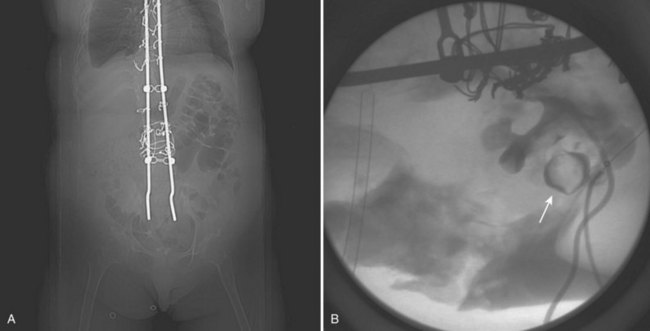

Circumstances that require special consideration involve children with spinal cord injuries and congenital anomalies such as spina bifida. In these patients, positioning can be a challenge due to existing spinal hardware and limb contracture (Fig. 135–9) (Ost and Lee, 2006a). Patients who have had prior spinal surgery consisting of vertebral fusion or Harrington rod placement will have restricted spinal mobility, spinal curvature, and/or atrophic or contracted extremities (Fig. 135–10). As the result of scoliosis, lordosis, and/or kyphosis, renal anatomy is altered. Consequently, the risk of injuries to adjacent organs (i.e., pneumothorax) during percutaneous procedures increases. Assessing the degree of mobility in the trunk and extremities is crucial in planning for PCNL in these patients (Fig. 135–11). These patients must be placed in the most comfortable position possible without excessive contortion or flexion of the joints. Special attention must be paid to latex precautions in the myelomeningocele population, and, as in all cases, proper padding of pressure points is mandatory.

Figure 135–9 A, Severe scoliosis and complete staghorn calculus (arrow) in a 10-year-old partial quadriplegic. B, Spinal curvature and limb contractures (left arm) prevented optimal prone positioning. Care is taken to pad all joints in the prone position.